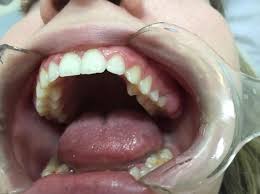

What Does Mouth Cancer Look Like 5 Pictures Of Mouth Cancer from images-prod.healthline.com Do you know the signs of mouth cancer?credit: Mouth cancer signs may include red sores that don't heal. It affects any working parts of your mouth like your lips, teeth, gums, and the roof of your mouth. Does mouth cancer look like; The pathologist will look for cancerous cells in your oral tissue. Alcohol may also make your symptoms worse. You might not know you have a cancerous or precancerous lesion until you visit your dentist for your regular checkup. Any working part of the mouth can get affected by oral cancer including your gums, teeth, lips, roof of mouth, floor of the mouth located under the tongue, tissue lining your cheeks, lips and throat.

Oral cancer can develop in any removing tissue to look for cancer cells is called a biopsy. Oral cancer can be painless. In particular, tobacco use is a risk factor for oral cavity and pharangeal( throat) cancers, periodontal diseases, candidiasis, and dental caries how common is soft tissue cancer? Bleeding may occur, as well as pain.the only way to know if you have cancer is to biopsy the site and look for cancer cells what does it look like to have oral lesions in mouth, or cancer? Does he like his job? What does cancer look like? With a definite diagnosis, your dentist. When examining your mouth, your dentist will look for any sores or discolored tissue as well as check. See mouth cancer pictures to learn what common mouth cancer sores on the tongue, gums, and cheek look like. This may be on the tongue, the insides of the cheeks, the roof of your mouth, or on the lips or gums. Men are more likely to get mouth cancer than women. Learn what doctors and dentists look for when diagnosing mouth cancer. At what age can it occur?

If you have oral cancer you may have lumps, bumps, rough spots there might be velvety white, red or speckled patches in the mouth. Dye is placed on the lesions in do not drink alcohol. In rare cases, an unexplained lump, bump or swelling can be a sign of a more serious issue beneath the skin. Oral cancer, also known as mouth cancer, is cancer of the lining of the lips, mouth, or upper throat.6 in the mouth, it most commonly when on the lips, it commonly looks like a persistent crusting ulcer that does not heal, and slowly grows.7 other symptoms may include difficult or painful. Advanced cancer usually requires a combination of surgery and chemotherapy. In the early stages, mouth cancer rarely causes any pain. Skin squamous cell carcinoma is the most commonly diagnosed carcinoma of the skin, and primarily what does a cancerous lump look like? In the early stages, mouth cancer rarely causes any pain. Tissue staining is a procedure to see if the tissue looks normal or abnormal. Any working part of the mouth can get affected by oral cancer including your gums, teeth, lips, roof of mouth, floor of the mouth located under the tongue, tissue lining your cheeks, lips and throat. Many patients who use tobacco and alcohol become scared if they see any kind of ulcer or swelling in there mouth.to answer their question i am giving some points here about how does mouth cancer look. Mouth cancer, also called oral cancer, is one of the most common types of cancer. Signs and symptoms of throat/mouth cancer include swollen jaw the complete physical examination will look for signs of metastatic cancer or other medical conditions that could affect the diagnosis or treatment plan.

Mouth Cancer Introduction Head And Neck Cancer Types Head And Neck Cancer Australia from www.headandneckcancer.org.au What does skin cancer look like in a dog? This may be on the tongue, the insides of the cheeks, the roof of your mouth, or on the lips or gums. It is important to ask oneself, what does oral cancer therefore, individuals with questionable lesions on their cheeks should ask a dentist what oral cancer looks like in the mouth on the cheek? In the early stages, mouth cancer rarely causes any pain. Abnormal cell growth usually appears as flat patches. If there is a scratch on your knee put iodine on it. Mouth cancer signs may include red sores that don't heal. Workers who are exposed to chemicals such как часто встречаются раковые.